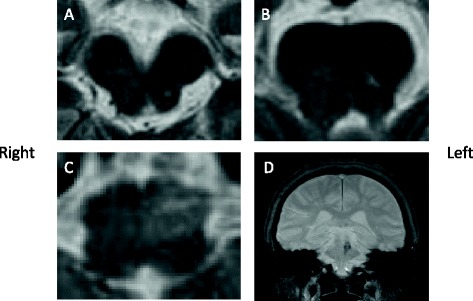

Hematologic and biochemical blood tests were normal. Magnetic resonance imaging (MRI) showed an old focus of the hemorrhage in the left pontine tegmentum, and T2-weighted imaging revealed a high signal intensity area in the left inferior olivary nucleus of the medulla oblongata (Figure 1). A surface electromyogram showed irregular grouped discharges at a rate of about 4 Hz in the brachialis and forearm muscles. Transoral carotid ultrasonography [6] was performed to evaluate the palatal abnormal movement. M mode imaging revealed rhythmic movements of the levator veli palatini muscle and pharyngeal wall with a frequency of 3 Hz; this was diagnosed as palatal tremor (Figure 2). Subtotal scores of Part A (tremor localization/severity rating), Part B (specific motor task/ function rating) and Part C (functional disabilities resulting from tremor) of the Clinical Rating Scale for Tremor (CRST) [7] were 10, 19, and 20, respectively, and a total score of CRST was 39.

Figure 1.

Magnetic resonance images 11 months after the onset of hemorrhage. The hemorrhagic focus in the left tegmentum (A, B, T2-weighted images). High signal intensity in the left medulla oblongata indicating hypertrophic olivary degeneration (C, T2-weighted image). Hemosiderin ring around the lesion in the left pontine tegmentum (D, coronal view, Fast Field Echo-weighted image).